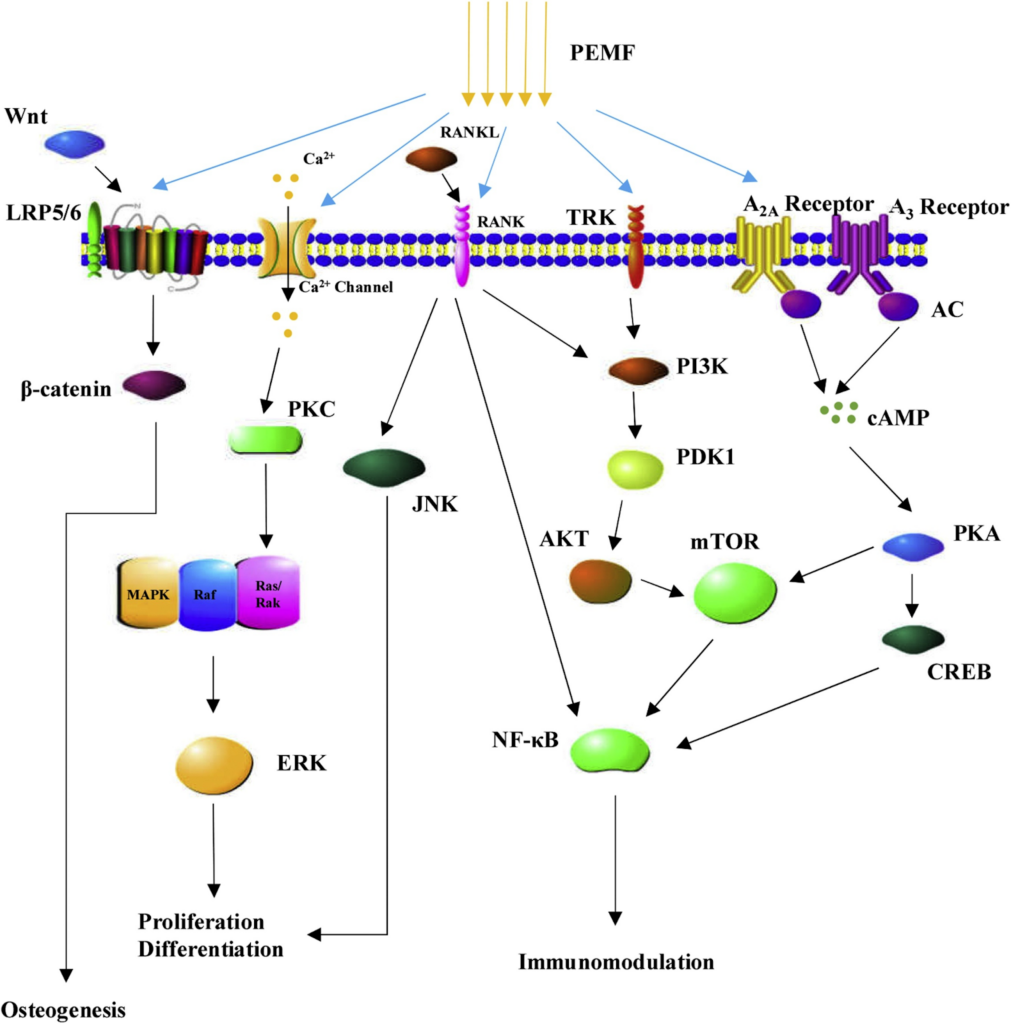

Molecular mechanisms of biological effects induced by low frequency electromagnetic fields

A recent review summarized the underlying signaling pathways of PEMFs, including Ca2+, Wnt/β-catenin, mitogen-activated protein kinase (MAPK), fibroblast growth factor (FGF), and vascular endothelial growth factor (VEGF), transforming growth factor (TGF)-β/ bone morphogenetic proteins (BMP), insulin-like growth factor (IGF), Notch, and cAMP/protein kinase A (PKA), in bone repair [49]. Furthermore, the mammalian target of rapamycin (mTOR) pathway has also been demonstrated to be the underlying signaling pathway of PEMFs involved in bone formation [50]. Of note, PEMF exposure also affected the synthesis of growth factors such as IGF [51], BMP [52], TGF-β [53], and PGE2 [54], promoting the synthesis of extra-cellular matrix (ECM) proteins and facilitating tissue repair [6].

LPEMF stimulation is involved in the regulation of cell proliferation and differentiation as well as immune modulation and inflammation response through a variety of underlying molecular mechanisms.

Summary of abbreviations

PEMF Pulsed electromagnetic field

PKC Protein kinase C

MAPK Mitogen-activated protein kinase

ERK Extracellular signal-regulated kinases

RANKL Receptor activator of nuclear factor kappa-B ligand

RANK Receptor activator of nuclear factor kappa-B

JNK c-Jun N-terminal kinase

PI3K Phosphatidylinositide 3-kinases

PDK1 Phosphoinositide dependent protein kinase-1

AKT Protein kinase B

mTOR mechanistic target of rapamycin

cAMP cyclic adenosine monophosphate

PKA Protein kinase A

CREB cAMP response element-binding protein

NF-KB Nuclear factor-kappa B